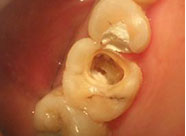

深齲蛀牙

牙髓發炎

根尖周炎

牙髓壞死

殘冠殘根

清理組織預備根管

嚴密根管填充